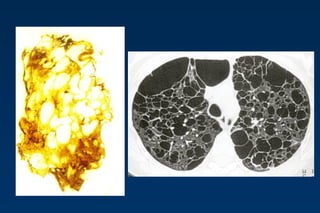

HONEYCOMBING

Defined as - small cystic spaces with irregularly

thickened walls composed of fibrous tissue.

Predominate in the peripheral and subpleural

lung regions

Subpleural honeycomb cysts typically occur in

several contiguous layers. D/D- paraseptal

emphysema in which subpleural cysts usually

occur in a single layer. 62